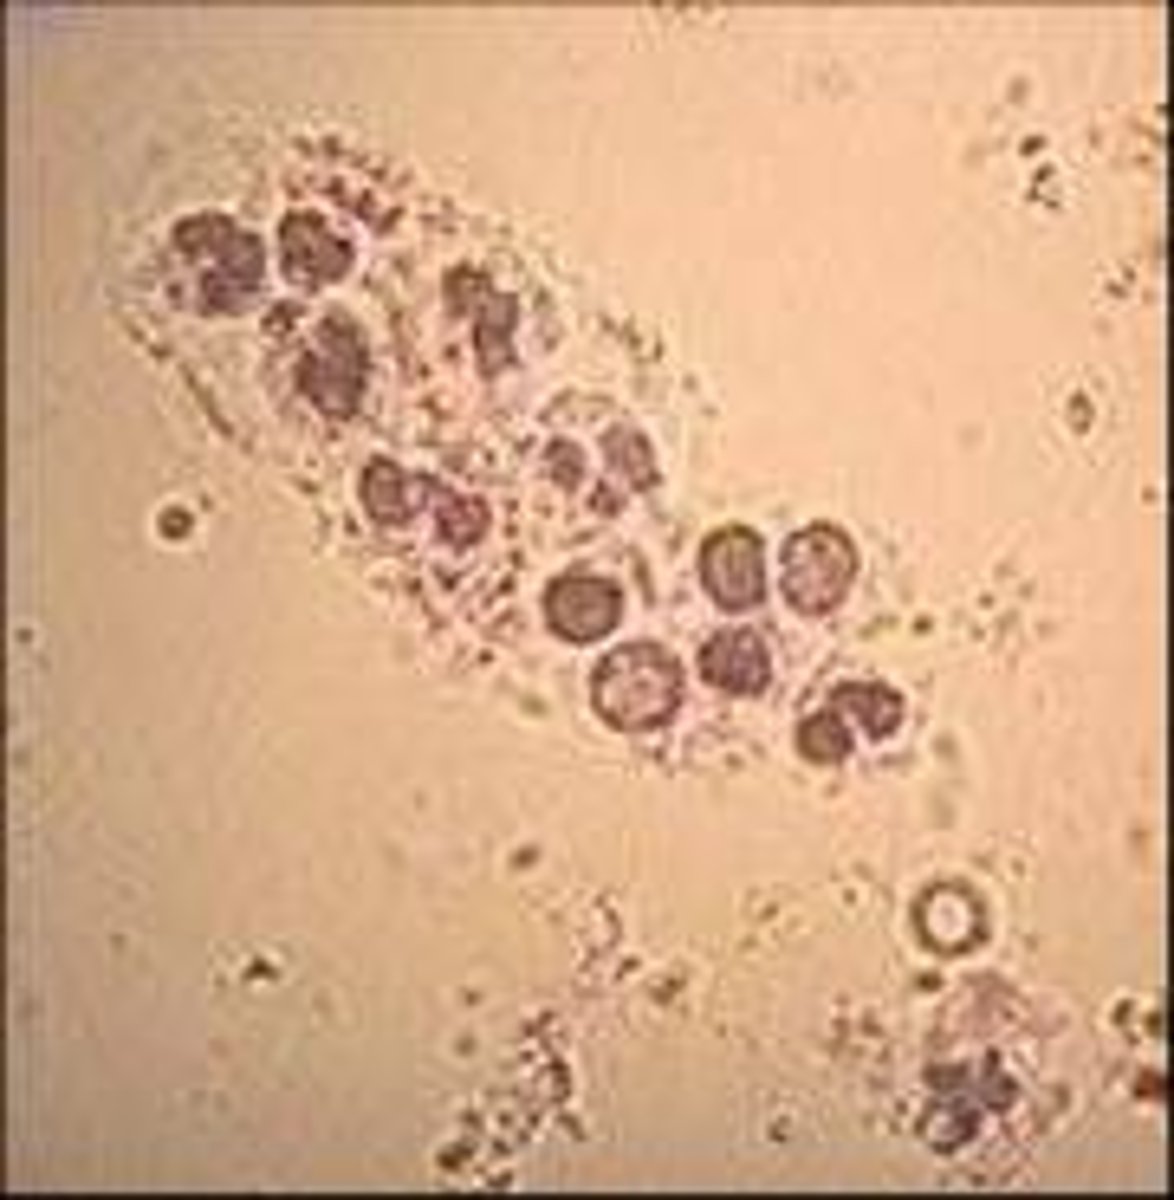

toxic neutrophils

MAMMAL

1. increase basophilia in cytoplasm

2. dohle bodies

3. vacuolated/foamy cytoplasm

4. +/- increase in cell size

dohle bodies

MAMMAL